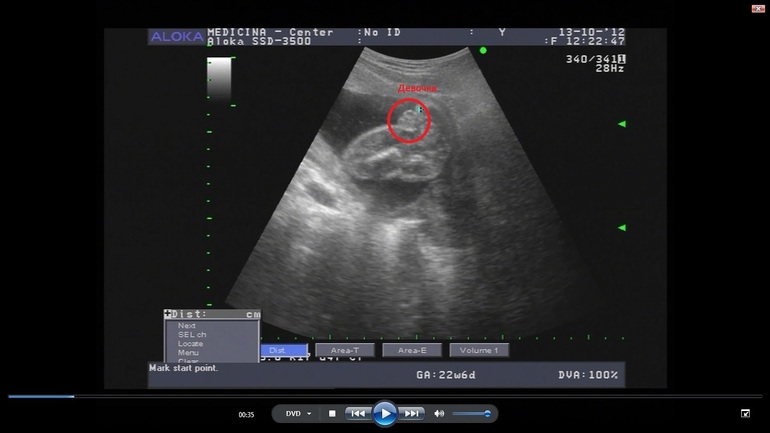

У меня, если что, вот так выглядели. Это дочка.

Это сынок. Тут в кадре только мошонка. Писюн сверху (в кадр не попал).Обе фотки - стоп-кадры видео, как бы вид снизу между ножек.